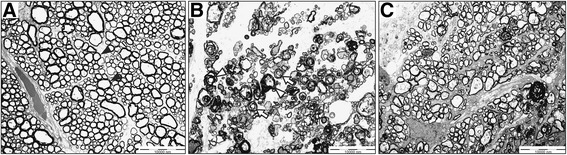

We compared the axon morphology and density in cross sections of the optic nerve under TEM. Four weeks after induction of acute ischemia, the optic nerve showed markedly greater axonal disorder than did that of sham-treated controls; this disorder was characterized by axonal swelling with separation of the myelin sheath, increased variability in axonal size and shape, and decreased axonal density (Fig. 1a and b). However, the axons in eyes treated with 1.0 mg/kg of etanercept for 4 weeks maintained a more normal configuration and a density similar to that of the control axons (Fig. 1c).

Fig. 1.

Etanercept prevents axonal damage secondary to ischemic injury. a-c Transmission electron micrographs of cross sections through rat optic nerves. a Normal compact axons with myelination and round shape in sham-treated control optic nerves (black arrowhead). b Axonal shrinkage with distortion of round shape and demyelination 4 weeks after acute ischemic injury. Separation of myelin sheath (white arrowhead) and a whorl-shaped mass (white arrow). c Relatively preserved round axons with myelination in ischemic model treated with 1.0 mg/kg etanercept. Original magnification: ×400; Scale bar, 10 μm